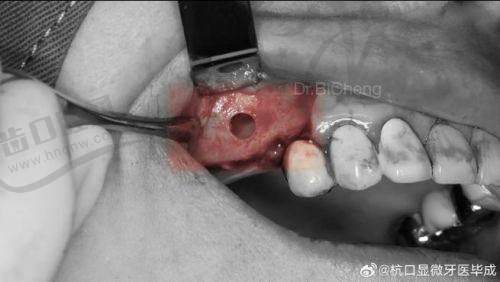

术后7 - 15天是伤口愈合的纤维增生期,此时创口处的胶原纤维开始大量形成,但新生组织非常脆弱。上颌窦黏膜在这个阶段正处于修复高峰期,会引发一系列连锁反应:

肿胀达到峰值:术后第3天开始肿胀明显,通常在5 - 7天达到高峰,而到15天时虽然整体消肿,但局部仍会有顽固性水肿

疼痛模式转变:从更初的锐痛转为钝痛,这种持续性不适往往比急性疼痛更难忍受

异物感显著:植入的骨粉与自体组织正在融合,会产生明显的胀满感和异物感

即公认的"更难熬阶段":

主要症状:持续钝痛、异物感、鼻塞、疲劳

护理重点:

保持伤口清洁,预防感染

逐步修复轻度活动,但避免劳累

注意饮食均衡,补充维生素C和蛋白质